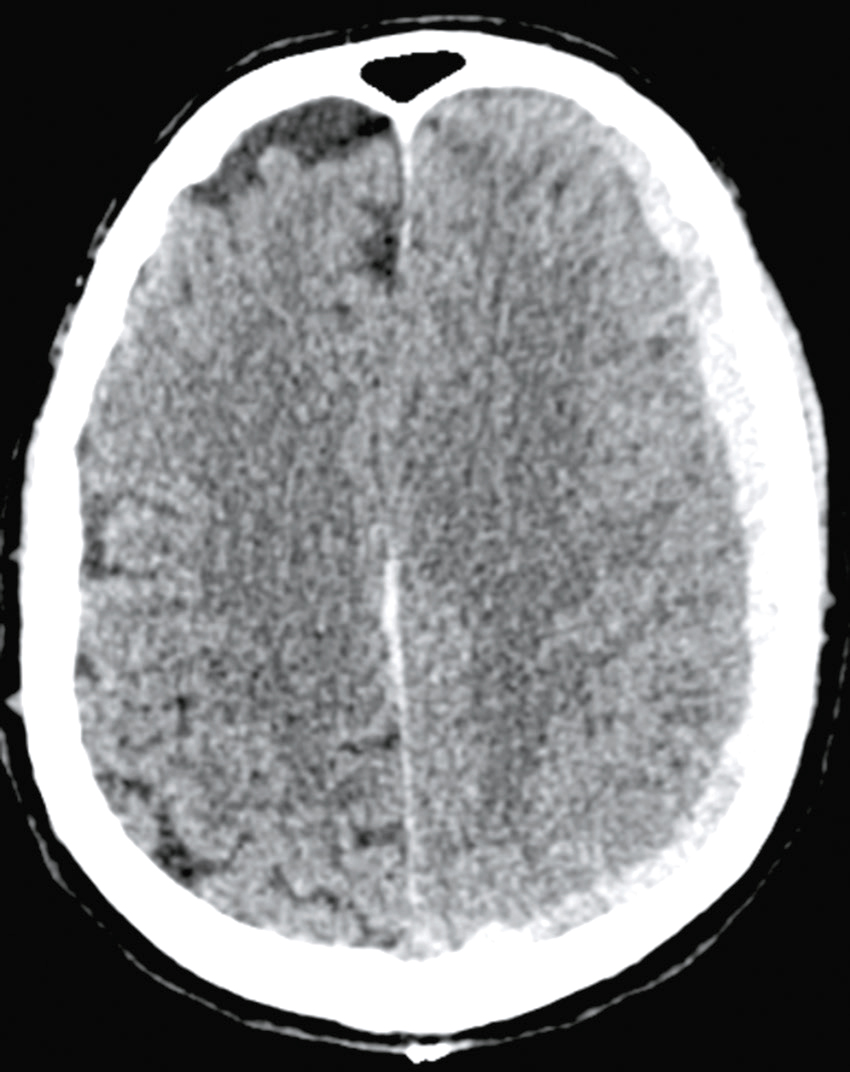

Une nouvelle IRM cérébrale est réalisée devant cette diplopie. Décrivez le cliché (fig. 31.1).

L'image montre une coupe transversale d'un cerveau humain obtenue par imagerie par résonance magnétique (IRM). Cette image est une vue axiale, ce qui signifie qu'elle est prise horizontalement à travers le cerveau. On peut observer les différentes structures cérébrales, y compris la matière grise et la matière blanche. Les ventricules latéraux, qui sont des cavités remplies de liquide céphalo-rachidien, sont visibles au centre de l'image. Les zones plus claires autour des ventricules peuvent indiquer des anomalies ou des lésions, souvent associées à des conditions neurologiques comme la sclérose en plaques. Les contours du cerveau sont bien définis, et les différentes régions du cortex cérébral sont clairement visibles. Cette image est intéressante car elle permet aux médecins de diagnostiquer et de surveiller diverses maladies neurologiques en visualisant les structures internes du cerveau avec une grande précision. L'IRM est une technique non invasive qui utilise des champs magnétiques et des ondes radio pour produire des images détaillées des organes et des tissus internes, ce qui est crucial pour la détection précoce et le traitement des maladies cérébrales.

- A coupe sagittale

- B séquence T1

- C hypersignaux de la substance blanche périventricu-laire

- D hypersignaux du tronc cérébral

- E hypersignaux juxtacorticaux